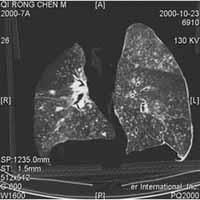

煤工塵肺2.X線檢查煤工塵肺胸片表現特徵有:網狀改變;結節狀改變;結節融合;塊狀陰影和多量絨毛狀改變。網狀改變被認為是煤工塵肺最早的表現,在肺野呈現瀰漫性細網狀陰影。而此時在臨床上無任何症狀。隨著結節的擴展,病變融合成不透明的進行性大塊纖維化,通常位於兩肺上野,也可跨肺葉融合至中、下肺野,有時僅發生在一側肺野,通常為大塊狀,均勻的、界限明顯的陰影。這些改變往往在單純性煤工塵肺彌散結節陰影的背景上發生。